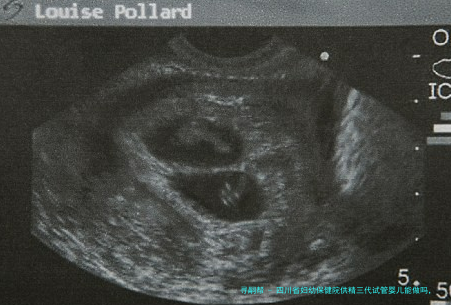

供精三代试管婴儿技术是利用第三代人类辅助生殖技术,将优质精子与女性卵子结合进行受精,然后将造成的胚胎移植到女性子宫内。该技术主要分为三代:第一代是指传统的试管受孕和胚胎移植(IVF),第二代是预implantation genetic diagnosis(PGD)基因检查筛选技术,第三代则是单细胞体基因诊断(NGS)技术,可以更准确地筛查胚胎的遗传信息。

供精三代试管婴儿技术能够帮助解决多种不孕不育症问题,例如男性精子偏少、质量差或存在遗传病等情况。四川省妇幼保健院享有专业的大夫团体和尖端的医疗配备,可以为患者提供质量高的供精三代试管婴儿服务。

试管移植流程一般分为以下若干个步骤:将通过检查筛选的优良胚胎经阴道形式移植到女性子宫内,手术之后需要卧床休息一阵子,并在移植后进行检测认定成功率。